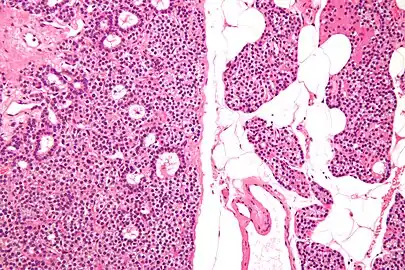

Micrograph of a parathyroid adenoma (left) and normal parathyroid gland (right). H&E stain.

Normal parathyroid gland with prominent adipose tissue is seen on the right of the image.-High magnification